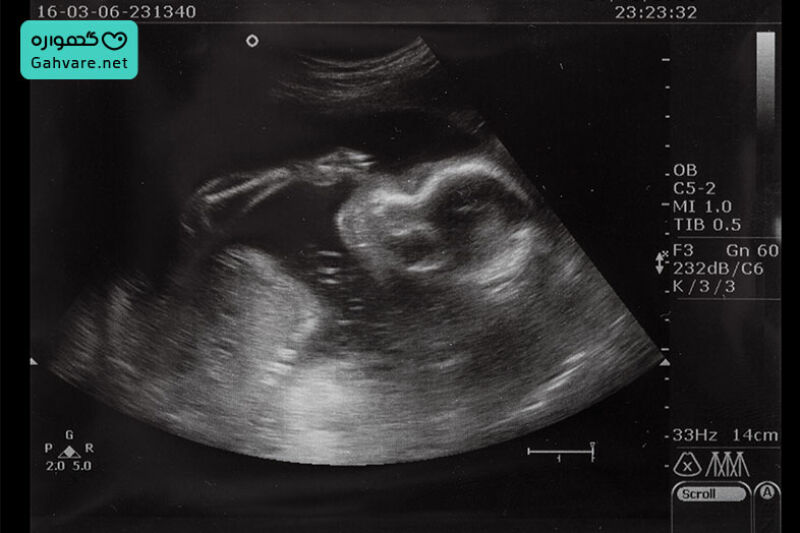

هفته سیزدهم نقطه رسمی ورود جنین به سهماهه دوم بارداری است؛ دورهای که رشد او با سرعت بیشتری ادامه پیدا میکند و حالا بیش از هر زمان دیگری شبیه یک انسان کوچک شده است. در این زمان طول جنین به حدود ۷ تا ۸ سانتیمتر میرسد و وزن او حدود ۲۰ تا ۲۵ گرم (در برخی اندازهگیریها حدود ۲۳ گرم) است.

آزمایشها و سونوگرافیهای لازم در هفته سیزدهم بارداری

آزمایشها و سونوگرافیهای لازم در هفته سیزدهم بارداری بخش مهمی از غربالگری سهماهه اول هستند و به تشخیص زودهنگام مشکلات کروموزومی، ارزیابی سلامت جنین و پیگیری وضعیت مادر کمک میکنند. در این هفته معمولاً نتایج آزمایشهای خون بههمراه سونوگرافی NT تفسیر میشوند تا احتمال اختلالاتی مانند سندرم داون، تریزومی ۱۸ و تریزومی ۱۳ مشخص شود. انجام این بررسیها در هفته ۱۳ بسیار اهمیت دارد زیرا آخرین زمان برای تکمیل غربالگری مرحله اول است و در صورت نیاز، پزشک میتواند روشهای تشخیصی تکمیلی مانند نمونهبرداری از پرزهای جفتی (CVS) را پیشنهاد دهد.

این بررسیها به پزشک کمک میکند ارزیابی دقیقی از وضعیت کروموزومی و رشد اولیه جنین داشته باشد و در صورت وجود مشکل، سریعاً اقدامات لازم انجام شود. با تکمیل غربالگریهای هفته ۱۳، مادر با خیال راحتتر وارد سهماهه دوم بارداری میشود.

تعیین جنسیت جنین در هفته سیزدهم بارداری

تعیین جنسیت جنین در هفته سیزدهم بارداری در برخی موارد امکانپذیر است، اما میزان دقت آن به روش استفاده شده بستگی دارد. در اواخر سه ماهه اول بارداری و حوالی هفته ۱۳، با افزایش طول crl جنین و شروع تمایز اندام تناسلی جنین، پزشک ممکن است در سونوگرافی بهویژه سونوگرافی NT حدسهایی درباره جنسیت مطرح کند، اما این تشخیص هنوز قطعی نیست.